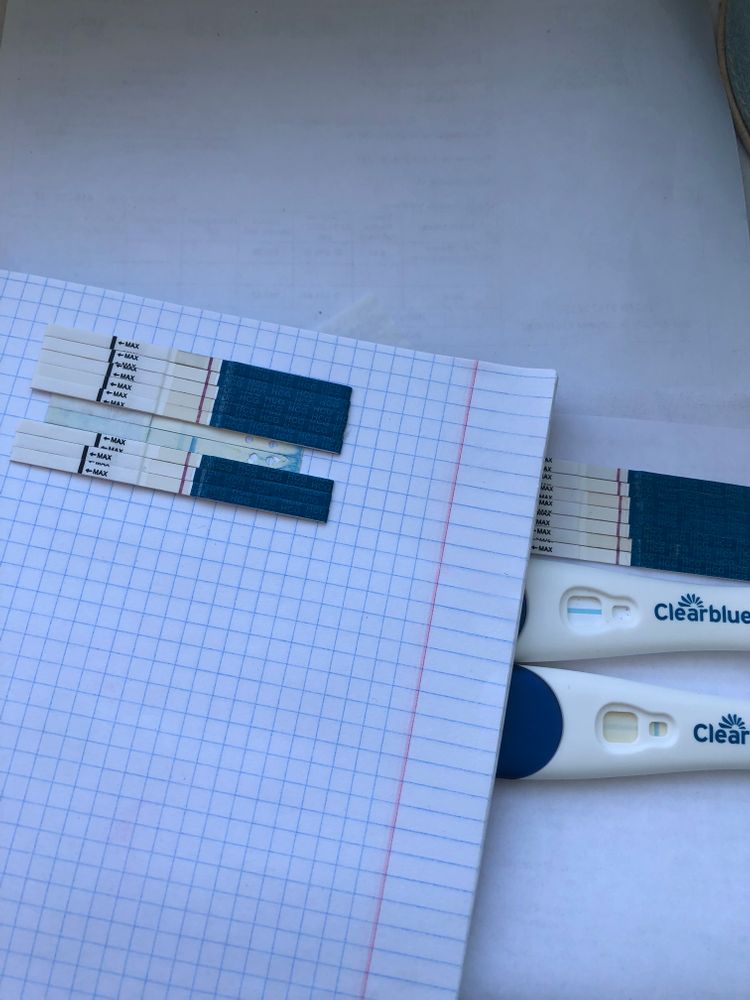

Я читала, что тесты на о показывают б. Возможно ли что и микроскоп на о, показал б.

Я уже ловила о в этом цикле, а по бт поймала из, ну как я думала, как тут вдруг. Вторая о или это первый признак б. Давайте попробуем разобраться. Подобного я р